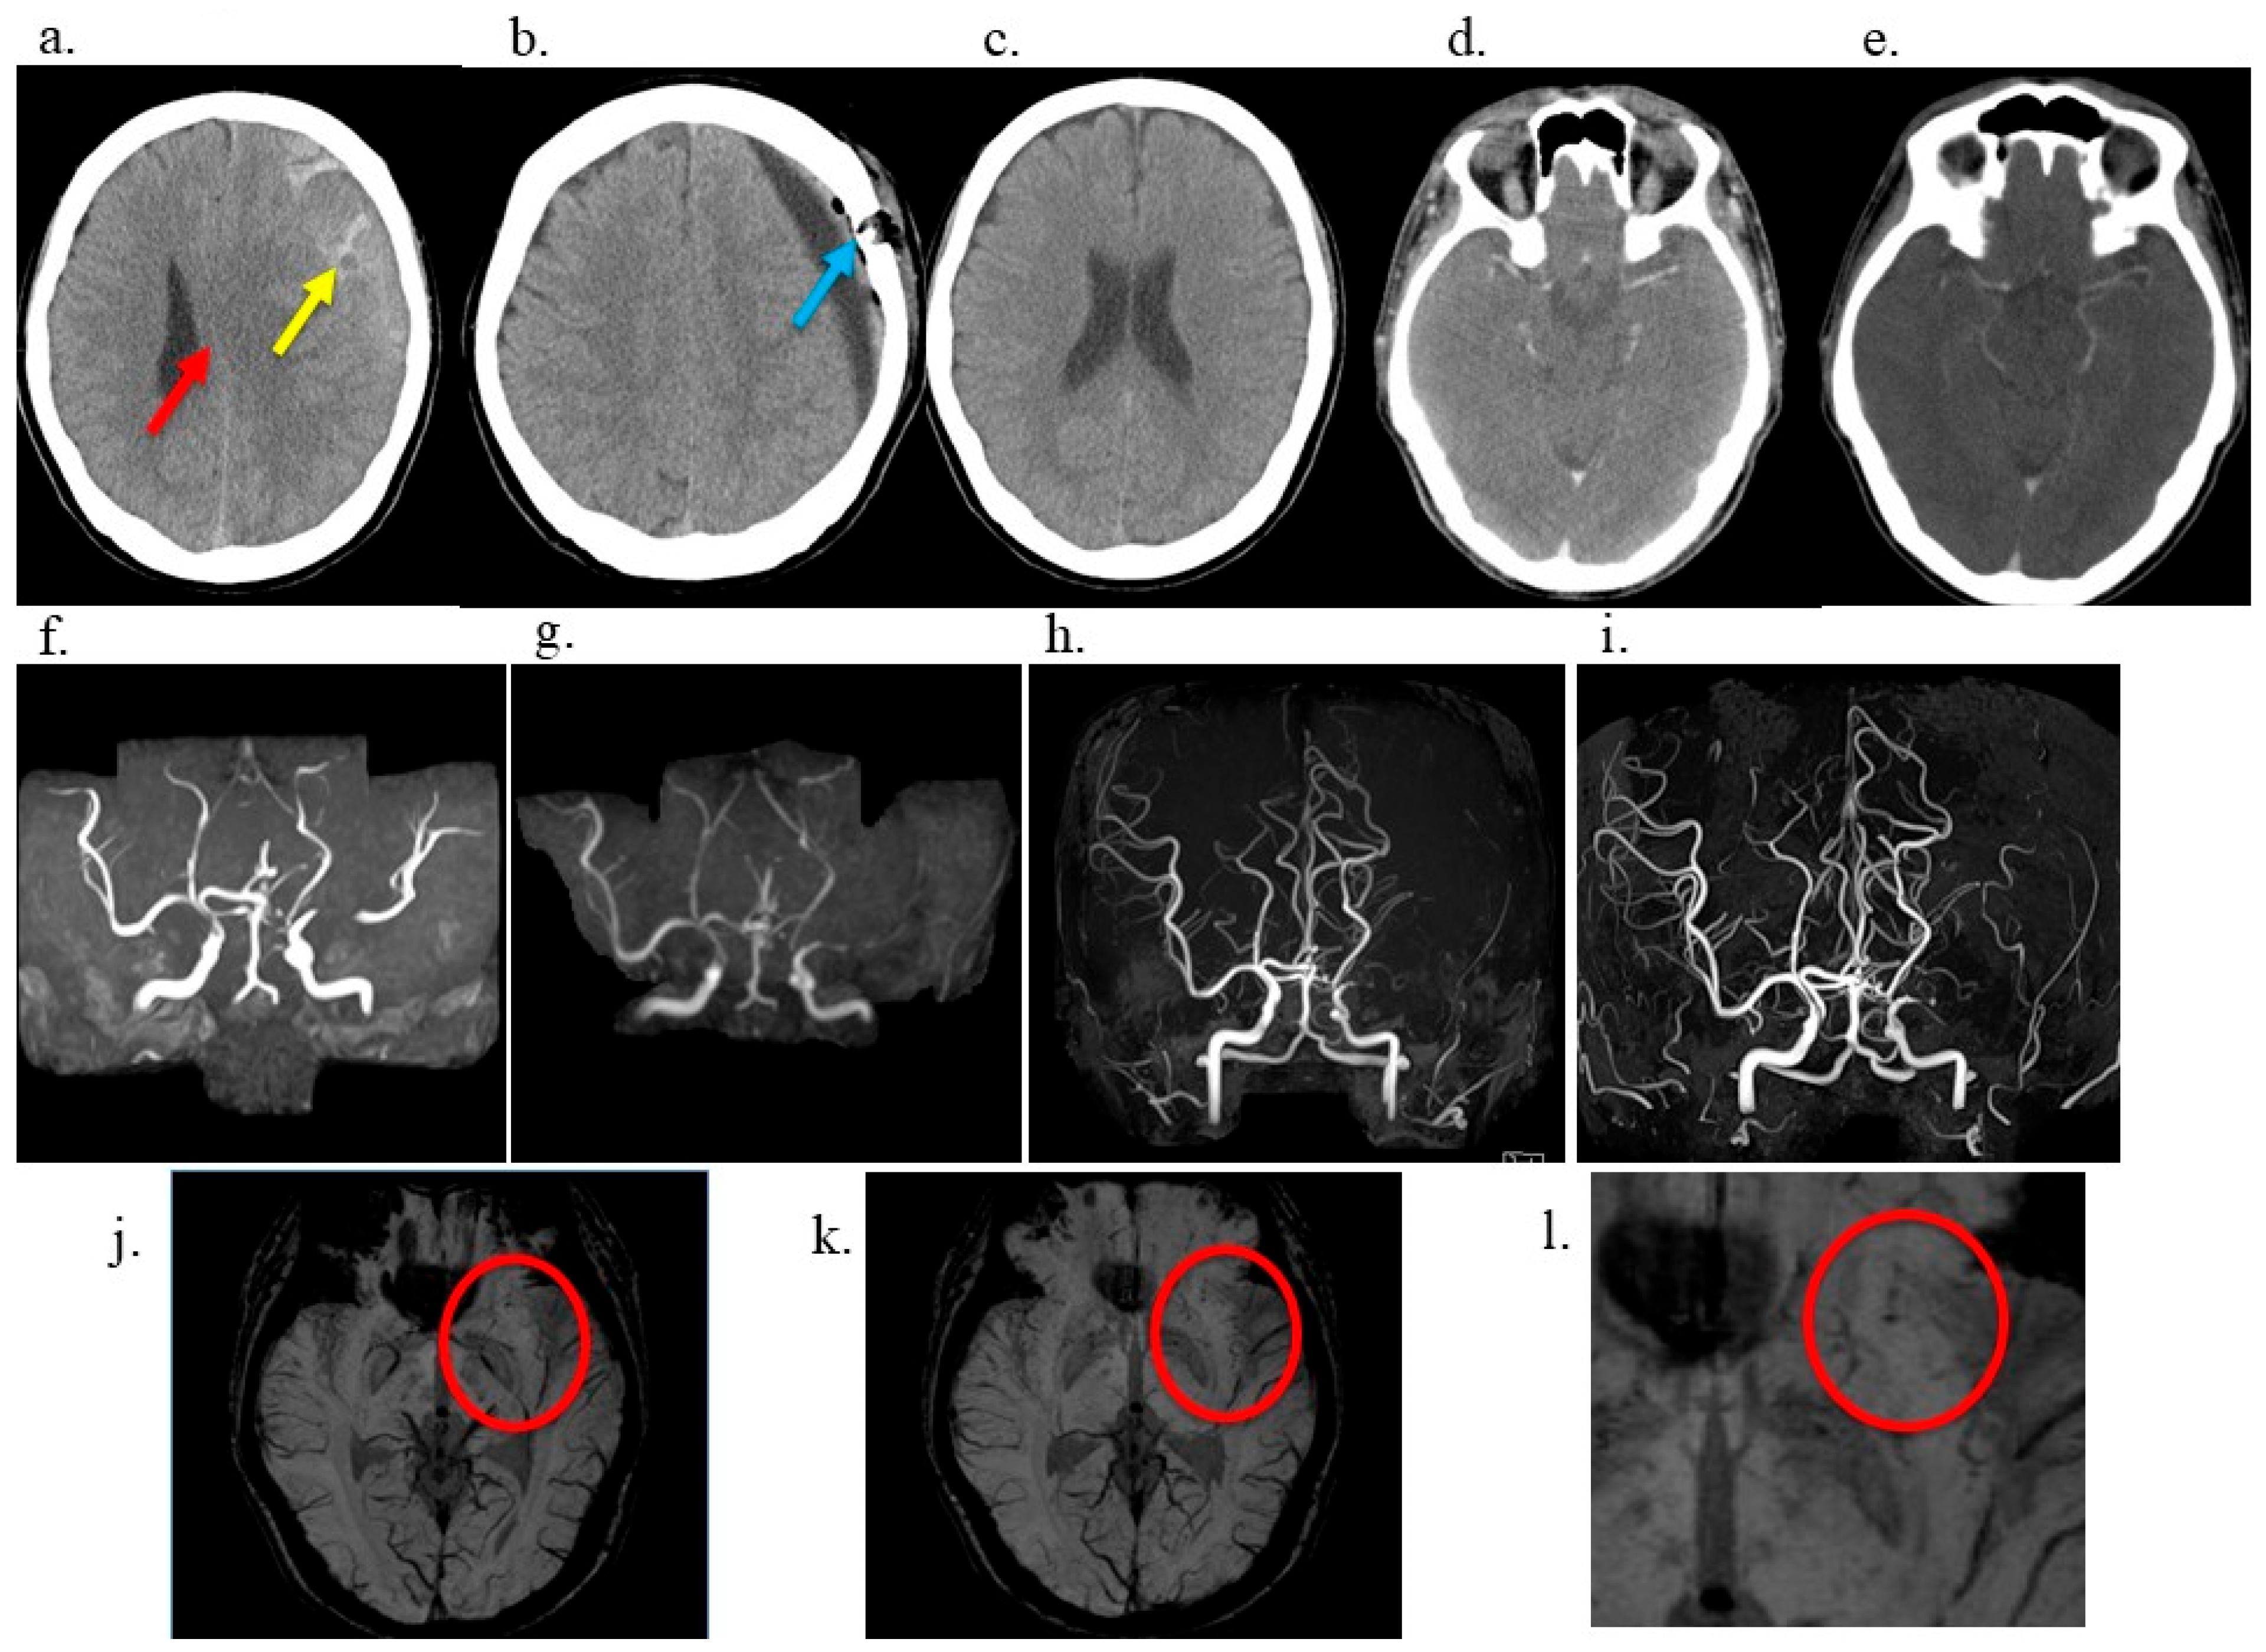

2. Case Description